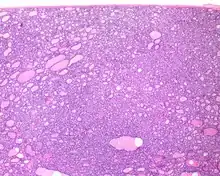

Histologic features

Several specific features must be identified for the tumor to be classified in this new category, while exclusion criteria should also be evaluated.

1) Encapsulated or partially encapsulated. The tumors are usually very well delimited or circumscribed, with the majority encapsulated, surrounded by a well formed fibrous connective tissue capsule.

2) Complete absence of invasion of any kind in a tumor that has been thoroughly and carefully evaluated with the whole capsule of the lesion sampled.

3) Predominantly follicular pattern of growth. Papillary structures should not be present. Further, solid, insular, or trabecular architecture must be <30% of the overall tumor for this category to still apply. Colloid (the material that thyroid follicular cells create) is easily identified throughout.

4) Must have the characteristic nuclear features of papillary thyroid carcinoma, although sometimes the features are patchy in distribution without all of the tumor showing those features. The nuclear features can be divided into three main categories:

- Nuclear size and shape: nuclear enlargement, nuclear elongation, and nuclear overlapping and crowding. Loss of nuclear polarity, with nuclei at the lumen, middle, or basal zone of the cells is also a helpful finding.

- Nuclear membrane irregularities: irregular nuclear contours, nuclear grooves and folds, "rat-bites" or demi-lune formations, and the presence of intranuclear cytoplasmic inclusions.

- Nuclear chromatin characteristics: nuclear chromatin clearing, often with condensation or margination along the nuclear membranes, resulting in accentuated nuclear margins, glassy nuclei, or fine, even delicate, powdery nuclear chromatin.

These features have been recently validated by an international group of practicing general surgical pathologists, showing a substantial interobserver agreement with applying a Nuclear Standardized Scoring System.[17]